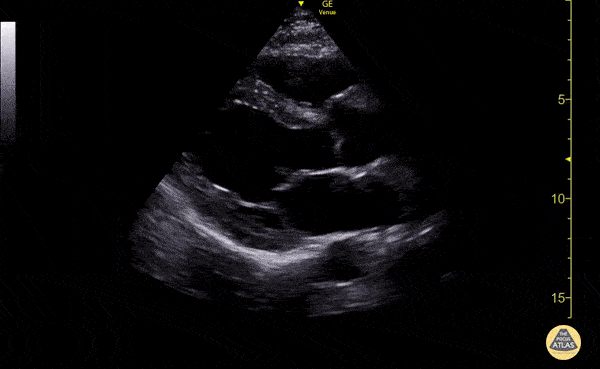

Sol ventrikül fonksiyonunun değerlendirilmesi

Sol ventrikül (LV) fonksiyonu dört pencerenin tamamında değerlendirilebilir; ancak genellikle parasternal uzun aks görüntüsünde en kolay şekilde incelenir. Değerlendirme iki şekilde yapılabilir:

Görsel (subjektif) tahmin

EPSS (End Point Septal Separation) ölçümü

Çok sayıda çalışma, acil hekimleri ile kardiyologlar arasında global kardiyak fonksiyonun görsel değerlendirilmesi açısından yeterli uyum olduğunu göstermiştir.

RUSH muayenesinde genellikle ejeksiyon fraksiyonunun tam yüzdesine odaklanmak yerine, sol ventrikül fonksiyonunu geniş kategoriler halinde sınıflandırırız:

Hiperkinetik (hiperdinamik)

Normal

Azalmış (düşük)

Azalmış sol ventrikül fonksiyonunu düşündüren hızlı ve pratik bulgular şunlardır:

Sol ventrikül kavite çapının sistolde yaklaşık üçte bir oranında küçülmemesi

Miyokardın sistol sırasında yeterince kalınlaşmaması

Mitral kapağın ön yaprağının diyastolde septuma yaklaşmaması

Buna karşılık hiperdinamik bir kalpte, sistolün zirvesinde ventrikül duvarlarının neredeyse tamamen kollabe olup birbirine temas ettiği izlenir.